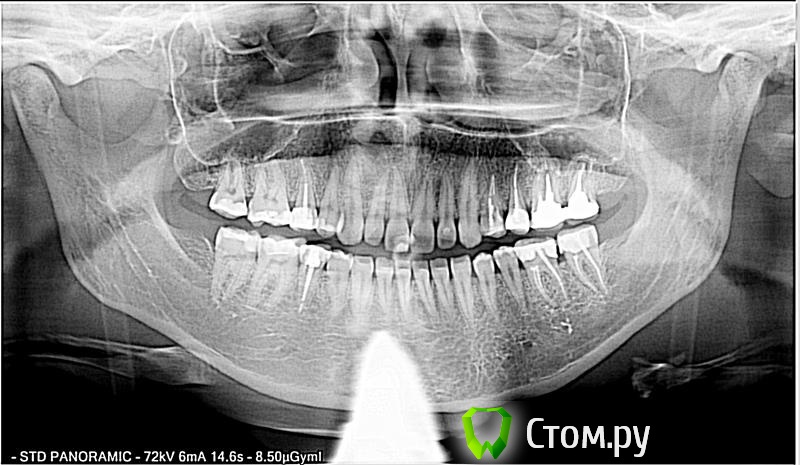

Фини7 Опубликовано 13 ноября, 2013 Поделиться Опубликовано 13 ноября, 2013 (изменено) Здравствуйте! После чистки кармана прошло 6 дней (между 6 и 7 зубом слева, нижняя челюсть). До сих приходится периодически пить обезболивающие, т.к. ноющая боль не проходит. Само место надреза воспаленное. Лечение: пока полощу хлоргексидином. Через некоторое время буду делать коронки на эти два зуба.Врач в отпуске, решила обратиться к вам. Пожалуйста, подскажите, является ли нормой такой срок для болезненных ощущений? На всякий случай прикладываю снимок. Изменено 13 ноября, 2013 пользователем Фини7 Ссылка на комментарий

Фини7 Опубликовано 13 ноября, 2013 Автор Поделиться Опубликовано 13 ноября, 2013 На всякий случай еще панорамный снимок. Ссылка на комментарий

IvanK Опубликовано 13 ноября, 2013 Поделиться Опубликовано 13 ноября, 2013 Здравствуйте. У Вас на зубах нависающие края пломб и на 6 и на 7. Обратитесь к Ортопеду. Зубы нуждаются в протезировании. 3 Ссылка на комментарий

Bier Опубликовано 13 ноября, 2013 Поделиться Опубликовано 13 ноября, 2013 +1 пока не поменяют пломбы (в идеале на коронки), ничего там не пройдет. Но перед этим еще каналы перелечить нужно 1 Ссылка на комментарий

Bier Опубликовано 13 ноября, 2013 Поделиться Опубликовано 13 ноября, 2013 ну карман образовался из-за нависающих пломб. Далее все по замкнутому кругу, не пройдет, пока не уберете причину. 1 Ссылка на комментарий